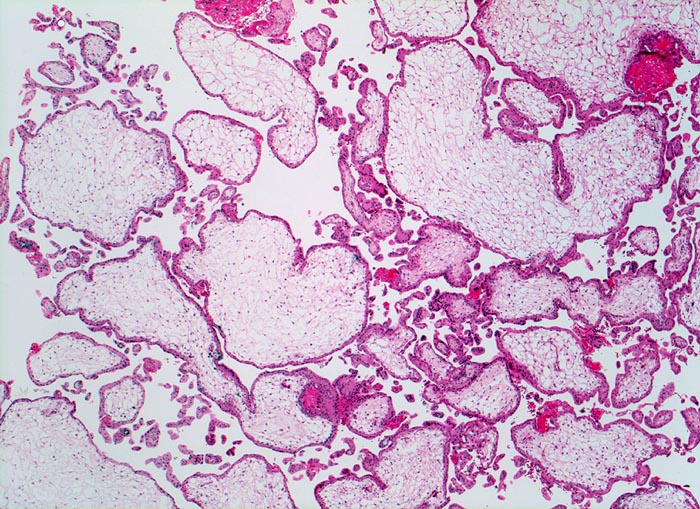

Partialmole bei Triploidie

Grosse plumpe mangelhaft verzweigte Zotten. Mangelhafte Vaskularisation und hydropische Umwandlung des Stromas der Plazentarzotten.

Karyotyp 69, XXX

29 jährige mit Abort in der 8. SSW

Im Gegensatz zur Mole nur geringe Trophoblastproliferation. Bei Partialmolen liegt ein diploider Chromosomensatz des Vaters und ein haploider der Mutter vor. Triploidien lassen sich bei etwa 15% chromosomal bedingter Aborte nachweisen. Triploide Früchte erreichen nur extrem selten Geburtsreife.